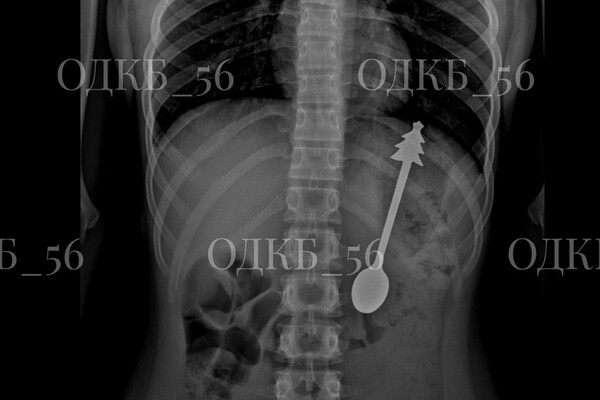

Врачи извлекли 14-сантиметровую ложку из желудка ребенка в Оренбургской области. Об этом сообщила пресс-служба регионального министерства здравоохранения на странице в социальной сети «ВКонтакте».

По данным ведомства, несовершеннолетний случайно проглотил ложку, после чего его срочно госпитализировали. Бригада скорой помощи доставила ребенка в детскую больницу, где ему сделали рентген органов брюшной полости. В результате выяснилось, что инородное тело находится в желудке.

«В экстренном порядке проведено <...> эндоскопическое удаление инородного предмета — металлической ложки длиной 14 см. Постманипуляционный период протекал без осложнений», — говорится в заявлении.

Публикация дополнена фотографиями извлеченной из ребенка ложки. На кадрах видно, что на конце ручки столового прибора находится фигурка елки.